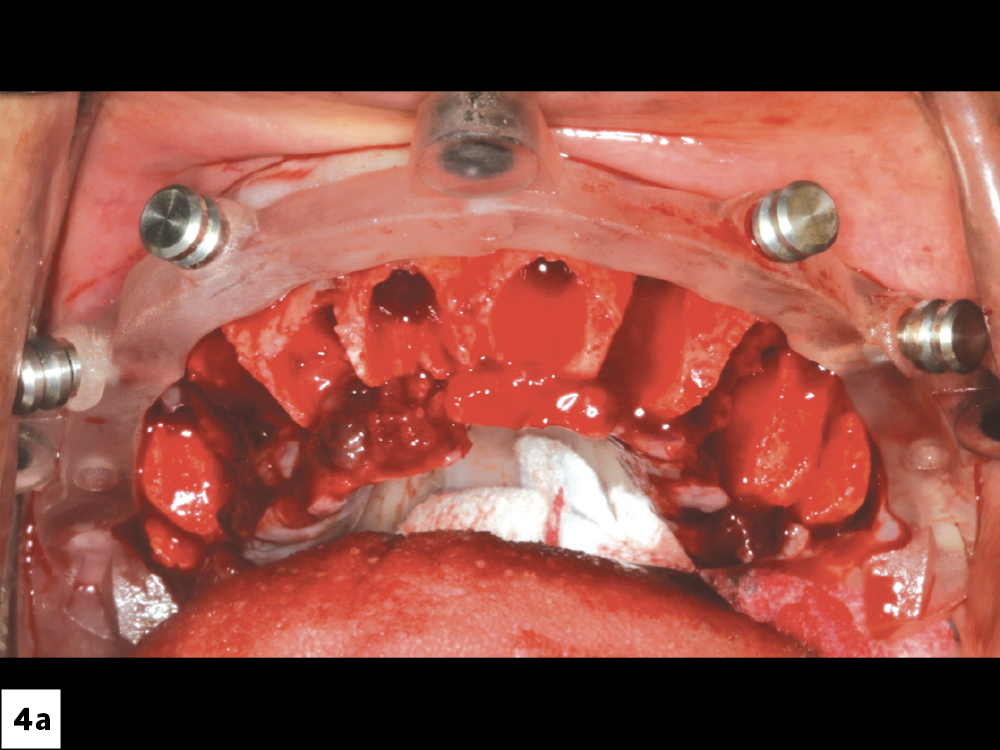

Figures 4a, 4b: First, I positioned the foundation guide. Using the bone reduction guide, excess bone was reduced in order to level the surface and provide 14–16 mm of interocclusal space for the restoration.